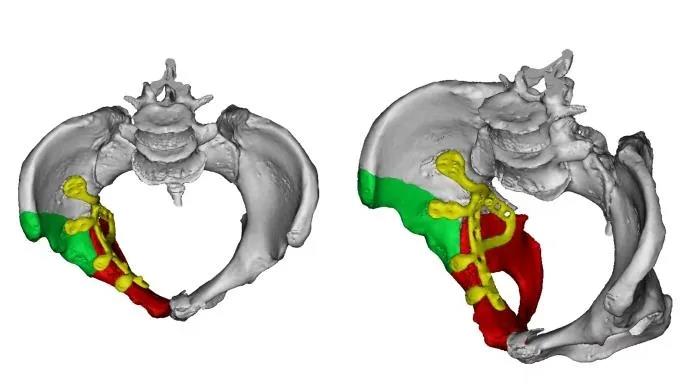

髋臼,作为连接躯干与下肢的“承重碗”,其解剖结构复杂、生物力学关键,直接决定着人体负重、行走与平衡功能。复杂髋臼骨折因其位置深在、骨折类型多变、毗邻重要神经血管结构,长期以来被视为创伤骨科领域最具挑战性的手术。

▲髋臼周围血管神经分布